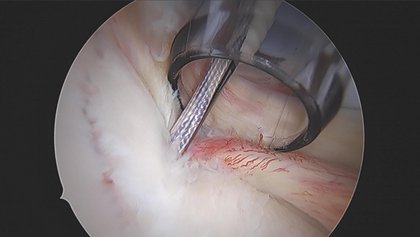

Sollte eine dieser Sehnen durch einen Unfall reißen kann diese mit speziellen resorbierbaren Ankern wieder befestigt werden. Dies geschieht über eine arthroskopische Operation, durch mehrere kleine Schnitte an der Schulter. Für die Naht darf der Riss nicht zu alt sein, da sonst der entsprechende Muskel seine Funktion bereits verloren hat. Ebenso darf die Sehne altersbedingt nicht zu sehr geschädigt sein, da sie sonst direkt wieder reißen würde.

Manchmal kommt es jedoch auch zum Abreißen der Gelenklippe, dem sogenannten Labrum. Die Gelenklippe heftet an der Schulterpfanne an um diese zu vergrößern und somit dem Oberarmkopf mehr Stabilität zu geben. Sollte die Gelenklippe abreißen und verschoben sein, wird sie nicht selbständig anheilen und die Schulter kann instabil verbleiben. Über eine Schulterspiegelung kann mit kleinen Ankern und entsprechenden Fäden die Gelenklippe wieder an die richtige Position angeheftet werden. Unter einem bestimmten Nachbehandlungsplan heilt das Labrum dann wieder an der richtigen Stelle fest und übernimmt seine Funktion der Schulterstabilisierung wieder.